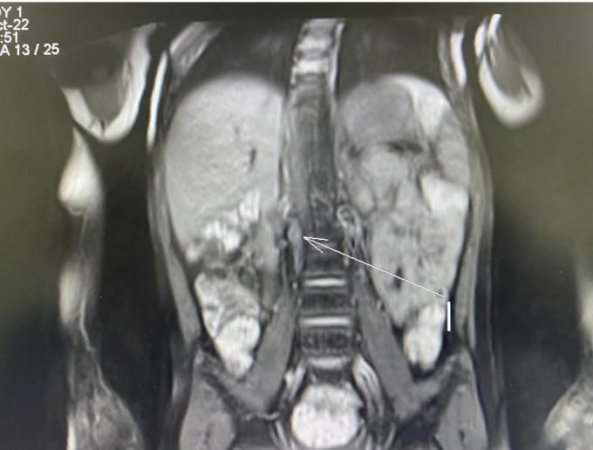

Нейробластома - это эмбриональная опухоль симпатической нервной системы, которая характеризуется агрессивным неуправляемым ростом и бурным метастазированием. Не смотря на разработанные схемы терапии прогноз для больных группы высокого риска остаётся неблагоприятным. Одним из достижений в лечении нейробластомы группы высокого риска является иммунотерапия с применением динутуксимаба бета (Карзиба), который позволяет повысить шансы на выздоровление данным пациентам. Однако применение Карзибы до недавнего времени не представлялось возможным ввиду его высокой стоимости и отсутствия регистрации.